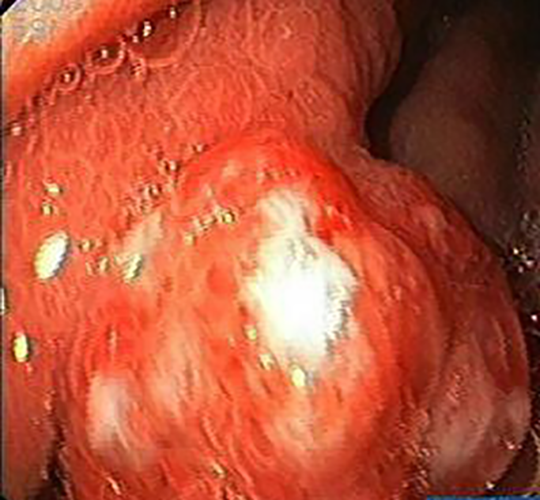

胃息肉圖片

胃息肉